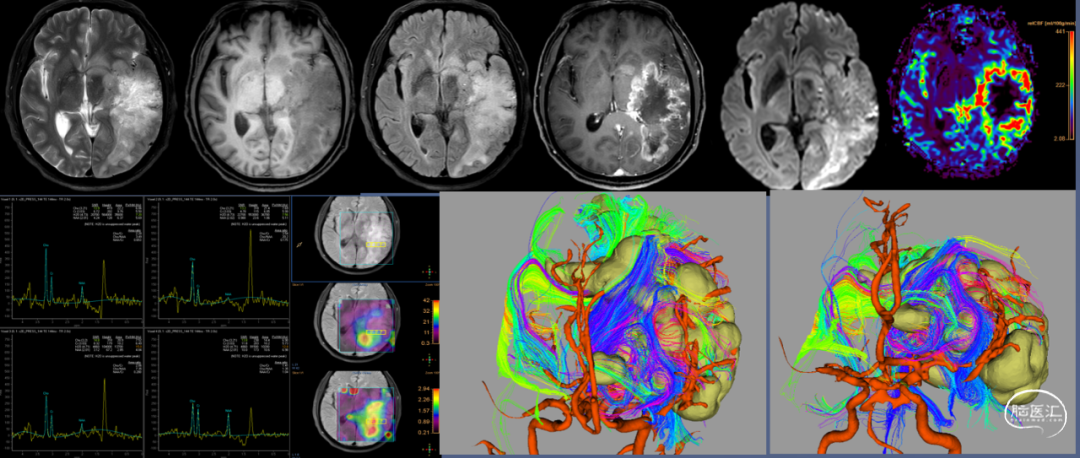

湖北省肿瘤医院影像科苏佳佳教授:该病例的脑磁共振并未显示除PPT展示部位之外的其他部位的病灶,对于脑胶质瘤的磁共振扫描,包括了T1加权、T2加权、DWI、T2 FLARE、灌注等等,相较于常规脑磁共振扫描更加全面,以更清晰准确的发现微小病灶及更好地区分胶质瘤与脑转移瘤特征。

华西医院影像科:该病例病变右侧基底节区,呈开环状强化,T2加权显示病灶主要位于内囊后支旁区域,包括丘脑、基底节、临近脑白质,临近的灰质边界清楚,延着白质方向,FLAIR加权更为明显,SWI未见明显出血,波普Cho/NAA值倒置,但是倒置不明显,比值没有超过2,影像诊断倾向非肿瘤病变,考虑免疫相关血管炎或瘤样脱髓鞘,瘤样脱髓鞘可能性更大。病灶延着白质区域,肿瘤也需要考虑,如胶质瘤。在进行免疫治疗后复查MRI,病变区域缩小,增强呈片状强化,Cho/NAA值倒置不明显。也进一步支持上述诊断。